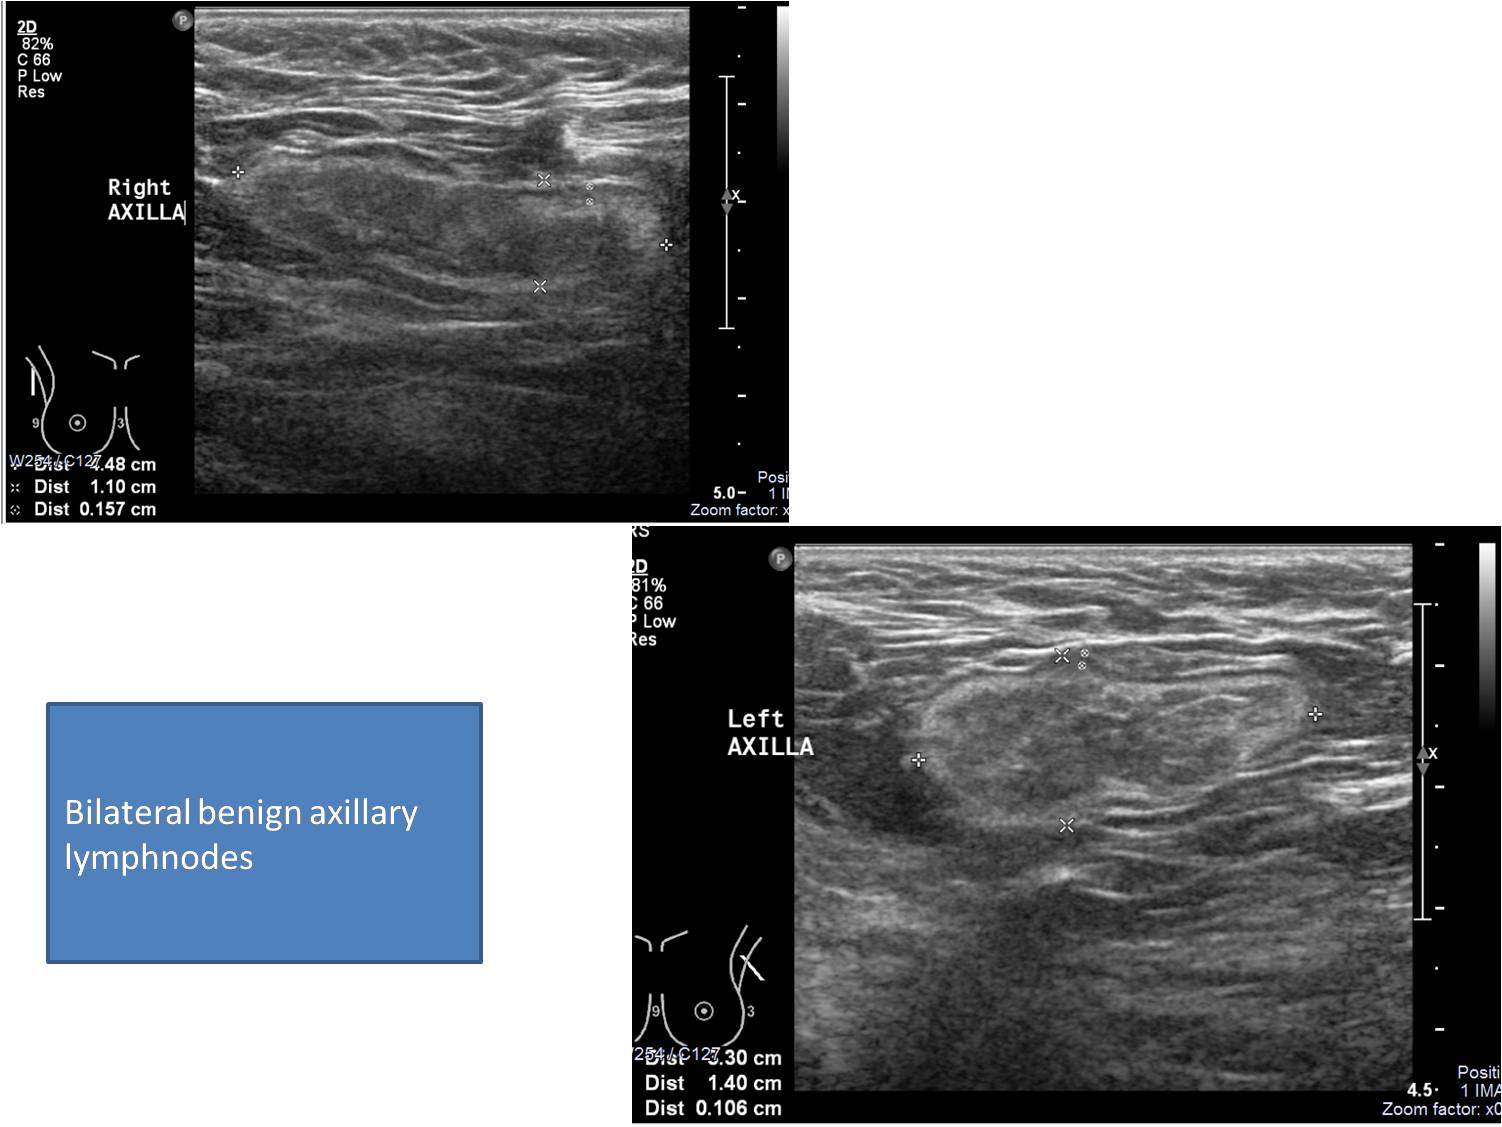

Mammography Right: upper central high density irregular shaped mass with spiculated margin. Nipple retracted. Left: upper central high density mass with spiculated margin. Nipple retracted. Ultrasound: findings described with images